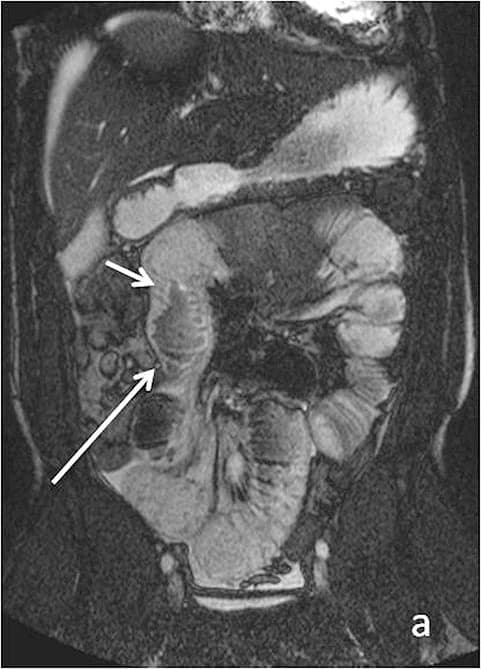

Magnetic resonance enterography (MRE) is now a key test for suspected or known Crohn's disease and, in some contexts, ulcerative colitis.

- Active inflammation in the bowel wall (thickening, increased blood flow, edema).

- Strictures (narrowed segments) that can slow or block food passage.

- Fistulas (abnormal tunnels) and abscesses around the intestines.

For someone whose “IBS” is actually undiagnosed Crohn's, these scans can change everything, from diet advice to the need for medication that targets inflammation rather than just masking symptoms.